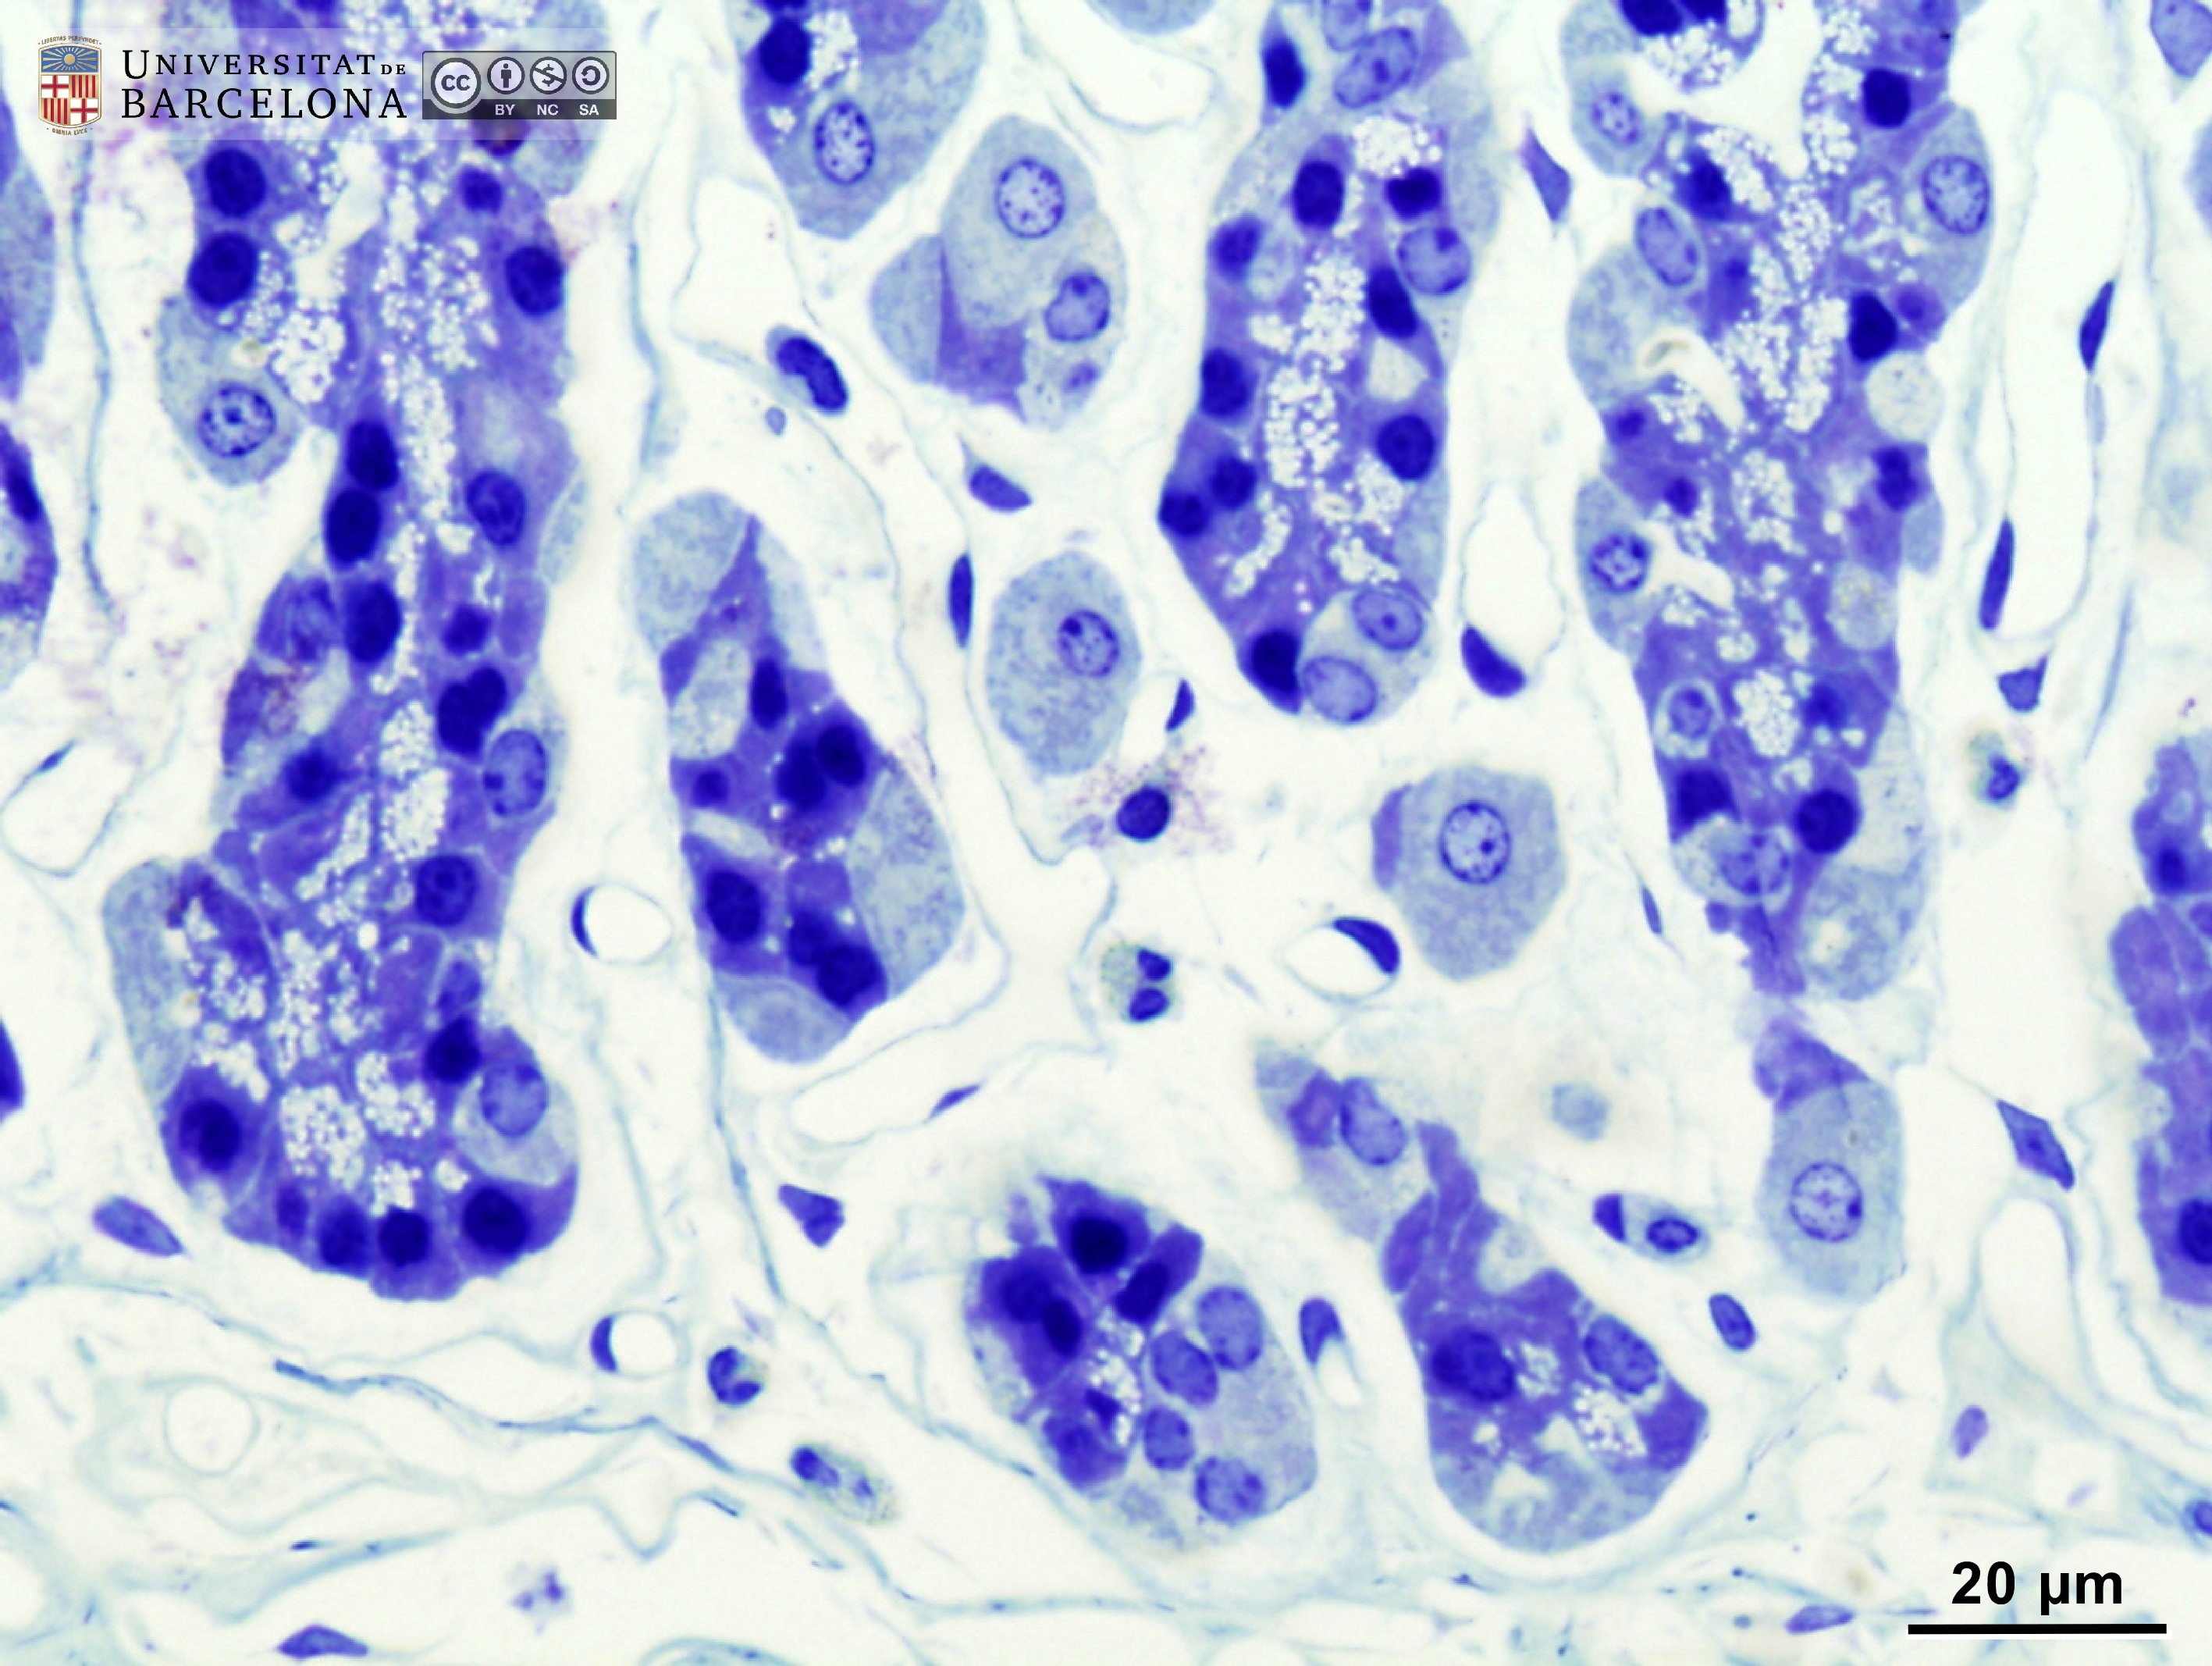

[ENG] A collection of micrographs illustrating the organisation of the stomach in rats. The layers of the gastric wall and their components –such as blood vessels, fibres and cell types– are shown in paraffin sections stained with hæmatoxylin-eosin stain or van Gieson trichrome. Semithin sections 2 µm thick were stained with toluidine blue. This collection complements the micrographs published by Dr Elena Sagristà i Mateo https://hdl.handle.net/2445/60213 — See also: https://diposit.ub.edu/dspace/browse?type=author&value=Sagrist%C3%A0+i+Mateo%2C+Elena

[CAT] Col·lecció de micrografies de l'organització de l'estómac de la rata. Es mostren les capes de la paret estomacal i els seus components (vasos sanguinis, fibres, tipus cel·lulars, etc.) en talls de parafina tenyits amb hematoxilina-eosina o el tricròmic de van Gieson i talls semifins de resina epoxi tenyits amb blau de toluïdina. Aquesta col·lecció complementa les micrografies publicades per la Dra. Elena Sagristà i Mateo https://hdl.handle.net/2445/60213 — I també: https://diposit.ub.edu/dspace/browse?type=author&value=Sagrist%C3%A0+i+Mateo%2C+Elena